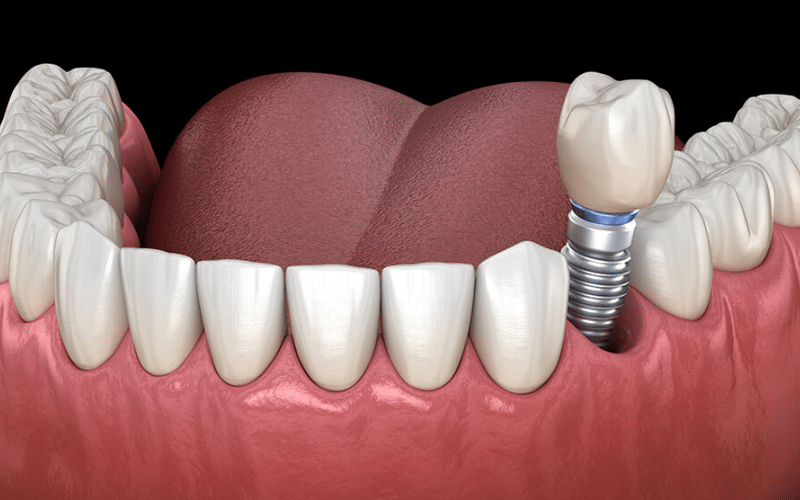

A dental implant is a small titanium post surgically placed into the jawbone to act as an artificial tooth root. Once integrated with the bone, it provides a solid foundation for a crown, bridge, or denture. The stability offered by dental implants mimics natural teeth, making eating and speaking significantly easier compared to other options.

- Surgical Placement: The implant post is carefully inserted into the jawbone. Over time, the bone fuses with the implant through a process called osseointegration, creating a durable foundation.

- Crown Placement: After successful integration, a custom-made crown is attached to the implant. This final step restores the tooth’s appearance and functionality.